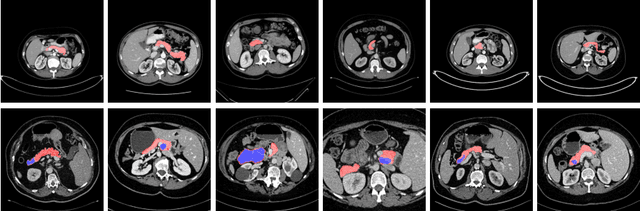

Abstract:This work presents comprehensive results to detect in the early stage the pancreatic neuroendocrine tumors (PNETs), a group of endocrine tumors arising in the pancreas, which are the second common type of pancreatic cancer, by checking the abdominal CT scans. To the best of our knowledge, this task has not been studied before as a computational task. To provide radiologists with tumor locations, we adopt a segmentation framework to classify CT volumes by checking if at least a sufficient number of voxels is segmented as tumors. To quantitatively analyze our method, we collect and voxelwisely label a new abdominal CT dataset containing $376$ cases with both arterial and venous phases available for each case, in which $228$ cases were diagnosed with PNETs while the remaining $148$ cases are normal, which is currently the largest dataset for PNETs to the best of our knowledge. In order to incorporate rich knowledge of radiologists to our framework, we annotate dilated pancreatic duct as well, which is regarded as the sign of high risk for pancreatic cancer. Quantitatively, our approach outperforms state-of-the-art segmentation networks and achieves a sensitivity of $89.47\%$ at a specificity of $81.08\%$, which indicates a potential direction to achieve a clinical impact related to cancer diagnosis by earlier tumor detection.